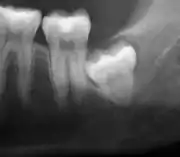

The diagnosis of impaction can be made clinically if enough of the wisdom tooth is visible to determine its angulation, depth, and if the patient is old enough that further eruption or uprighting is unlikely. Wisdom teeth continue to move to the age of 25 years old due to eruption, and then continue some later movement owing to periodontal disease.[18]

If the tooth cannot be assessed with clinical exam alone, the diagnosis is made using either a panoramic radiograph or cone-beam CT. Where unerupted wisdom teeth still have eruption potential several predictors are used to determine the chance of the teeth becoming impacted. The ratio of space between the tooth crown length and the amount of space available, the angle of the teeth compared to the other teeth are the two most commonly used predictors, with the space ratio being the most accurate. Despite the capacity for movement into early adulthood, the likelihood that the tooth will become impacted can be predicted when the ratio of space available to the length of the crown of the tooth is under 1.[5]: 141